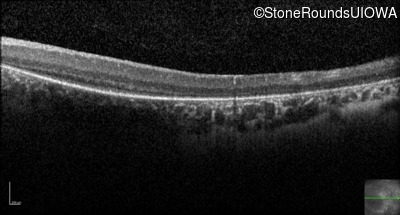

Optical Coherence Tomography - Right - No Light Perception

Exemplar / OCT Stack